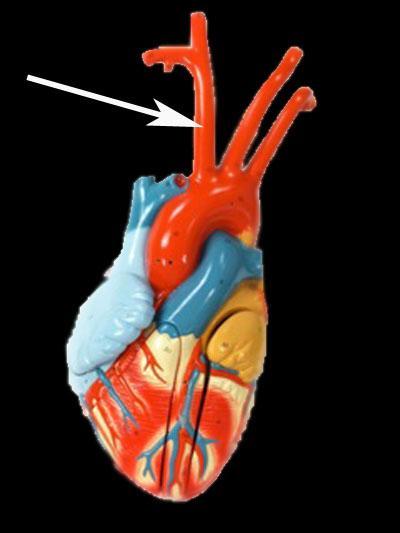

Aortic Arch

Brachiocephalic artery

Brachiocephalic vein